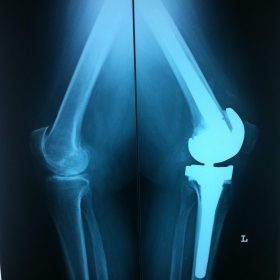

Σε αυτό το σημείο η Αρθροπλαστική Γονάτου αποτελεί μονόδρομο.